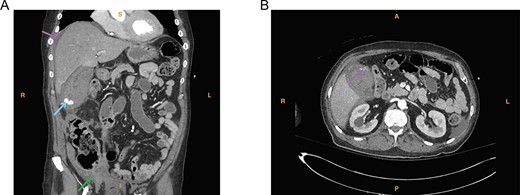

A 74-year-old man with a past medical history of type II diabetes mellitus, recent COVID-19 infection with prolonged hospital course and ventilator dependence requiring tracheostomy status post decannulation, coronary artery disease and myocardial infarction status post three-vessel coronary artery bypass graft in 1991 and drug-eluting stent placement in 2020 on dual antiplatelet therapy (DAPT; aspirin and clopidogrel) presented with acute onset epigastric and right upper quadrant pain that started 3 hours prior to presentation from a rehabilitation facility. In the emergency department, the patient was hypotensive (systolic blood pressure of 70 mmHg) with a transient response to crystalloid resuscitation. Laboratory studies revealed a hemoglobin of 8.9 g/dl, a hematocrit of 27%, leukocytosis (21.6 × 103/μl, normal range 4.3–10.8 × 103/μl), slightly elevated lactic acid to 1.9 mmol/L (normal range 0.3–1.9 mmol/l) and elevated creatinine serum to 1.43 mg/dl. Computed tomography of the abdomen and pelvis revealed a distended gallbladder containing multiple calculi and hyperdense intraluminal content (Fig. 1A). A prominent tortuous cholecystic artery branch was noted at the fundus (Fig. 1B). Hemoperitoneum with concern for acute hemorrhage was suspected, given fluid collection in the pericholecystic, perihepatic and perisplenic spaces.

(A) Computed tomography imaging from Case 1 showing a distended gallbladder with multiple calculi (cyan arrow) as well as hyperdense intraluminal fluid (magenta arrow) with collection in the pelvis (green arrow) consistent with hemorrhage. Present in the figure, the letters S, L, I and R denote superior, left, inferior and right, respectively. (B) Computed tomography imaging from Case 1 showing the tortuous path of a cholecystic artery branch (magenta arrow) at the gallbladder fundus. Present in the figure, the letters A, L, P and R denote anterior, left, posterior and right, respectively.